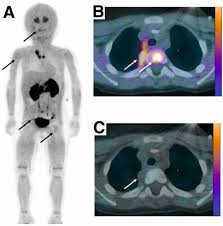

Slideshow 911 biomed

911 biomed